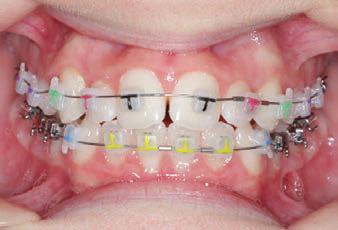

CLASS II DIV.1 - Marra

PROGRESS 1 - 26/9/18 - Class I platform accomplished in 5.75 months with Motion 3D COLOR Appliance

PROGRESS 2 - 26/9/18 - Placement of the SLX 3D Clear Brackets

with M-ONE .015 Cu Nitanium 27°

PROGRESS 3 - 30/10/18 - With M-TWO .020 x .020 Cu Nitanium 35° archwire

PROGRESS 4 - 27/11/18 - 3 links power chain: 5, 4, bypass 3 to crimp hooks

PROGRESS 5 - 13/3/19 - With M-TWO .020 x .020 Cu Nitanium 35° archwire

PROGRESS 6 - 1/8/19 - With M-THREE.019 x .025 Beta Titanium wire

FINAL - 10/10/19 - Appliances removed AFTER

PROGRESS 7 - 10/10/19 - Final day in SLX 3D Clear Brackets BEFORE